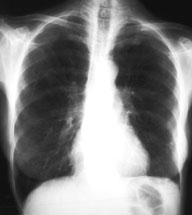

Eine 70-jährige Patientin meldet sich bei Ihnen in der Praxis mit Verschlechterung des Allgemeinzustandes seit 4-5 Wochen und Fieber bis maximal 38.5 Grad.

Des weitern klagt sie über einen trockenen Husten. Ausser einer arteriellen Hypertonie besteht als Vorerkrankung eine leichte COPD. Da Sie ausser dem Husten keinen klinischen Fokus für einen Infekt finden, entschliessen Sie sich für ein Thorax-Bild. Optimalerweise haben Sie sogar noch ein pa-Thorax von vor 2 Jahren zum Vergleich:

Thorax pa vor 2 Jahren

Bild vergrössern